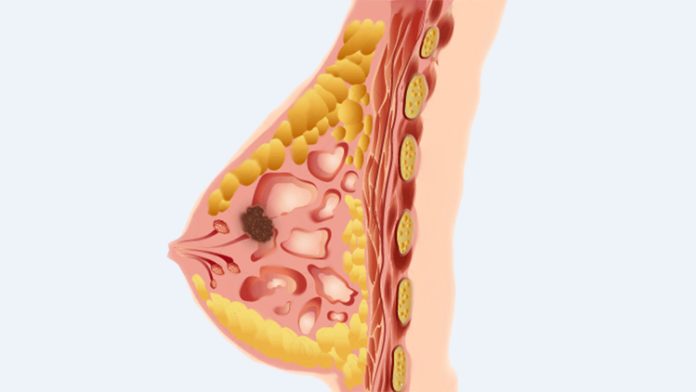

প্রাথমিক পর্যায়ে স্তন ক্যানসার দ্রুত শনাক্ত করতে পারলে এই রোগ পুরোপুরি নিরাময় করা সম্ভব। আর এ জন্য স্তন ক্যানসার স্ক্রিনিংয়ের গুরুত্ব অপরিসীম। স্তন ক্যানসার সম্পর্কে সঠিক ধারণা ও প্রয়োজনীয় সচেতনতা থাকলে স্ক্রিনিংয়ের মাধ্যমেই এই ক্যানসার অনেকাংশ নিয়ন্ত্রণ করা সম্ভব।

মেমোগ্রাফি স্তনের এক ধরনের এক্স-রে, যা স্তনে অন্য টিউমার আছে কিনা নির্ণয় করতে সাহায্য করে। প্রধানত দুটি উদ্দেশ্যে মেমোগ্রাফি করা হয়। স্ক্রিনিং মেমোগ্রাফি ও ডায়াগনস্টিক মেমোগ্রাফি ।

এসব পরীক্ষার মাধ্যমে চাকা বা পিন্ড পাওয়া গেলে টিস্যু ডায়াগনসিস বা বায়োপসি করে সঠিক রোগ নির্ণয় ও সঠিক চিকিৎসা দেওয়া হয়।